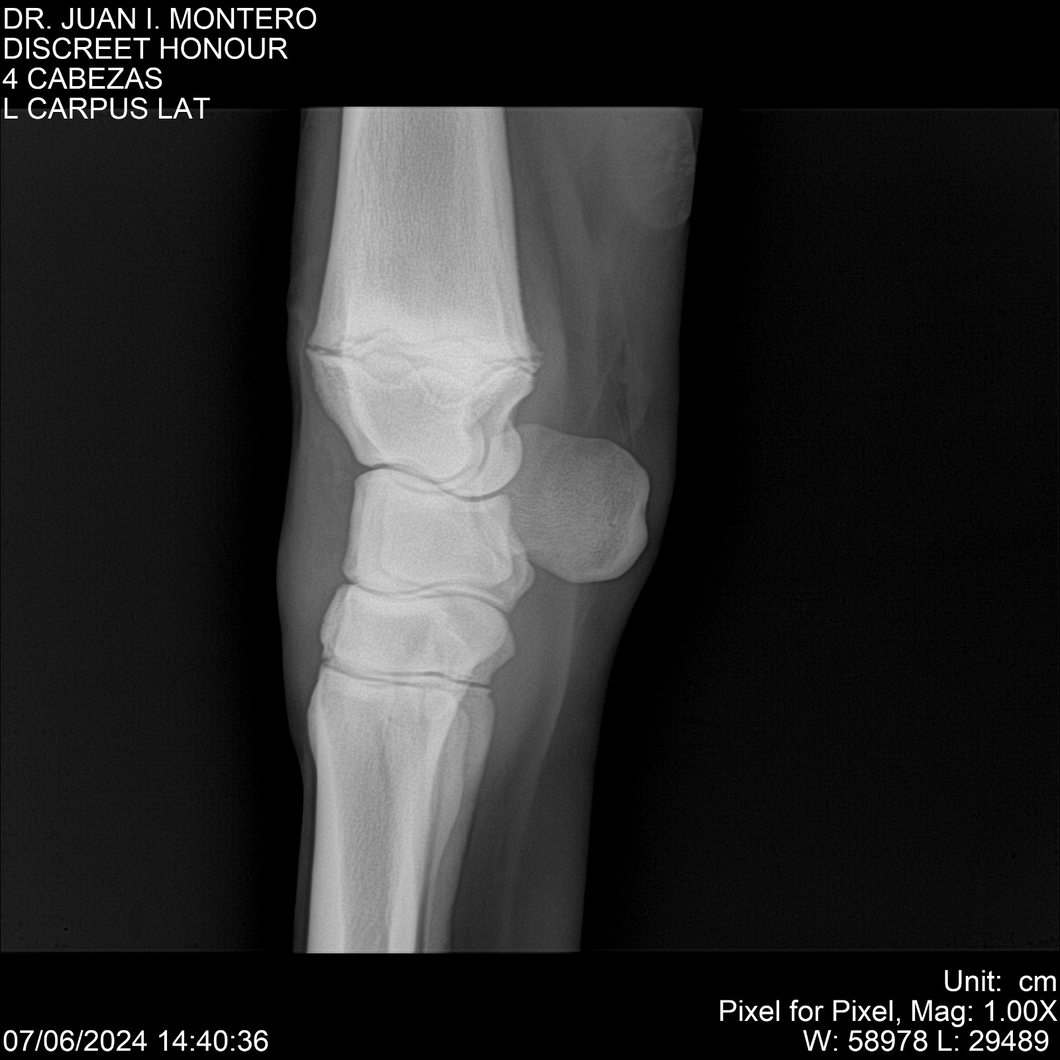

LOTE 6, DISCREET HONOUR 🔥 🔥 🔥 Lote Anterior Volver al remate Lote Siguiente Ficha Contacto Montevideo - Ficha del Lote Identificador: #281093 Categoría: Yeguarizos Montevideo - 82 Visualizaciones ClicData Contacto Empresa: Abelenda N. R., Walter Hugo Nombre*: Teléfono* : E-mail* : Mensaje Enviar Registrese gratis Este contenido Exclusivo está disponible sólo para usuarios registrados Ingresar